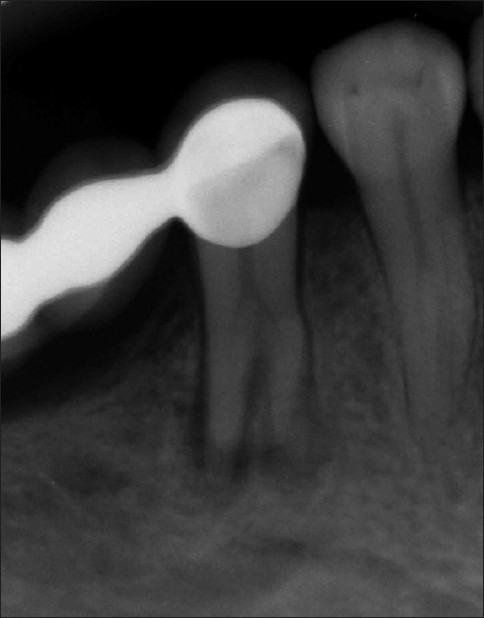

Mandibular second premolar with four roots

Sefika Nur Akyuz, Ali Erdemir

Detection of normal and abnormal variation in tooth anatomy is essential for clinical success. It is generally well known that the mandibular second premolar teeth have a single root and canal. However, the mandibular second premolar teeth have sometimes more than one root and root canal. The endodontic treatment of a mandibular second premolar with four roots which separated at different levels along the middle third of the root is presented in this case report. Preoperative radiographs appeared radiolucency and different root anatomy in the region of the mandibular second premolar. The root canals were prepared using Mtwo rotary system (VDW, Munich, Germany) and obturated laterally condensed gutta percha and AH plus (Dentsply De Trey, Konstanz, Germany). After the completion of root canal treatment, the tooth was restored with a posterior composite filling material. On follow-up, the tooth was clinically and radiographically asymptomatic for two years. Clinicians should be aware of the importance of careful clinical and radiographic examination of mandibular premolars during the endodontic treatment. Radiographs exposed at two different horizontal angles and their careful interpretation facilitates the search of additional root canals.